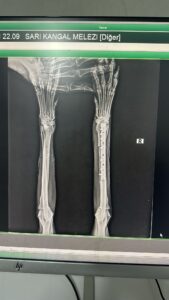

This dog, who came to the shelter with a broken leg, had surgery at Cadde Clinic. He’s doing well. He’s starting to walk again. Unfortunately, we don’t have a place to put him, so he’ll be returning to the shelter. He’ll be housed in a special place at the shelter until he can walk normally again. He’s a large dog suitable for shepherding sheep and cow farms. Male. 30 kg. 5-6 years old. Available for adoption from the shelter. We desperately need your support to care for this dog and many more. Please help us within your budget, so we can help them too.